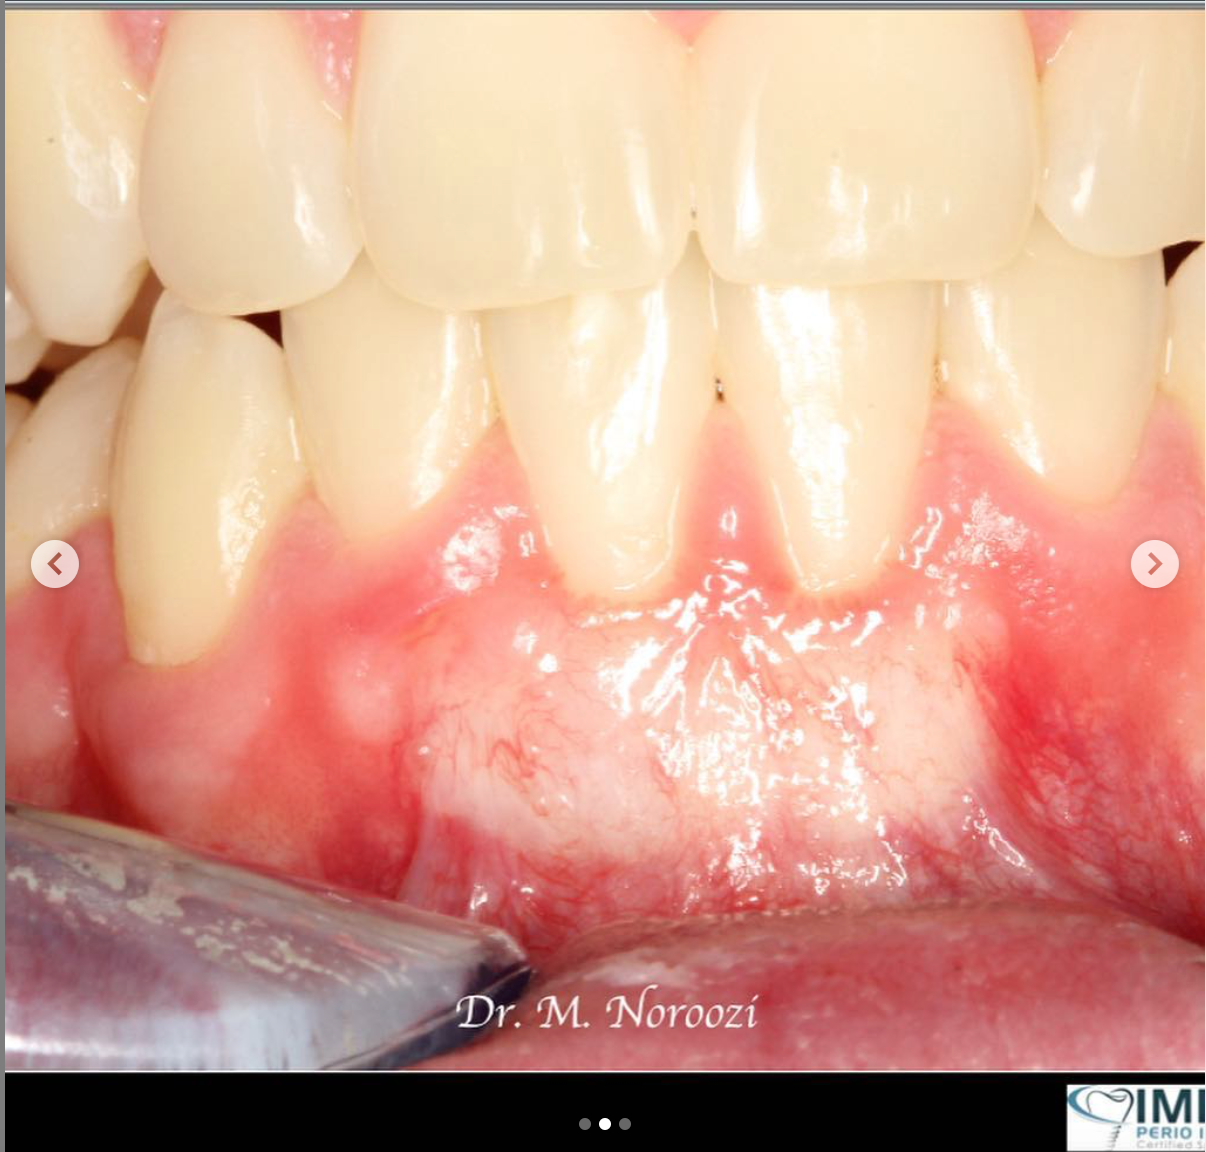

Allograft Dermal with Pinhole Surgery, Alternative to Gum Grafting

Connective Tissue Gingival Grafting for Gingival Recession